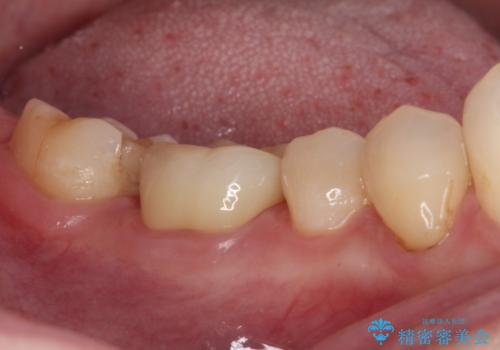

- セラミッククラウンが度々欠けてしまうとのことで来院された患者様です。

セラミッククラウンを装着するには、削る量がやや少ない印象であったので、クラウン破折リスクを回避するために削る量を少し増やすこととしました。

また、咬合力が強いため、強化セラミックのみで製作するフルジルコニアクラウンにて補綴治療することとしました。